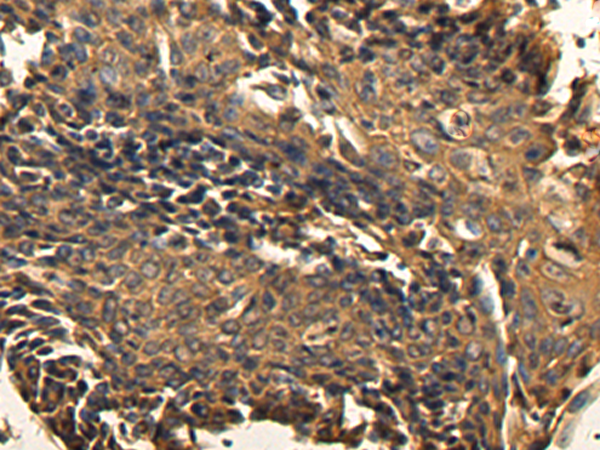

IHC positive control:

Human lung cancer

IHC Recommend dilution:

200-400